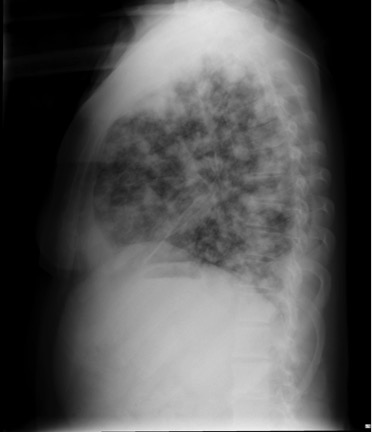

– Caso. Patrón nodular: opacidades redondeadas de muy pequeño tamaño normalmente difusas, con bordes netos, en número variable.

Causas:

- Granulomatosas: Tuberculosis miliar, Artritis reumatoide, Silicosis, Neumoconiosis, Sarcoidosis.

- Neoplasias: Metástasis (tiroides, riñón y melanoma).

- Otras: Proteinosis alveolar, Amiloidosis, Hemosiderosis, Microlitiasis alveolar.